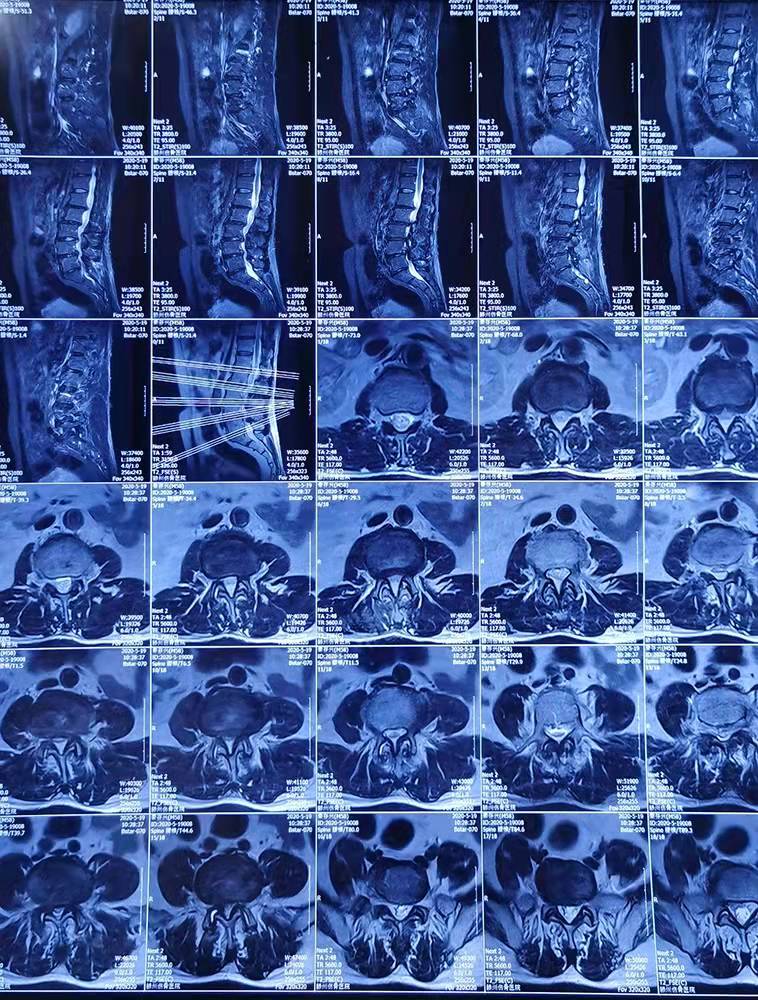

患者秦存興,男,59歲,腰痛多年勞累后加重,近一年來感腰痛伴雙側(cè)臀部、左大腿外側(cè)、小腿外側(cè)及右足麻木,行走50米后即感雙下肢疼痛劇烈,病痛的折磨給患者的生活帶來了很大的痛苦,讓他對(duì)未來失去了信心。來到誠(chéng)德骨科醫(yī)院

經(jīng)查體、X片、CT及核磁共振檢查后確診為腰椎管狹窄癥,腰椎退變性滑脫,與患者充分溝通后決定行腰1-腰5減壓植骨內(nèi)固定術(shù)